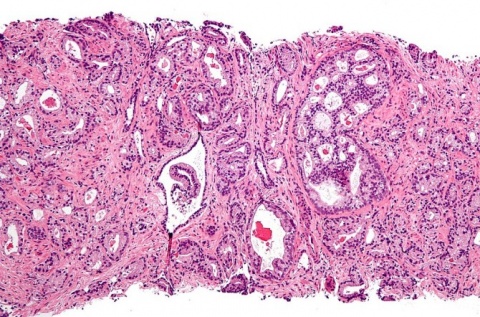

![[Img #58599]](https://noticiasdelaciencia.com/upload/images/01_2020/2653_buscan_facilitar_el_diagnostico_de_toxoplasmosis_en_embarazadas.jpg)

(Foto: Argentina Investiga)